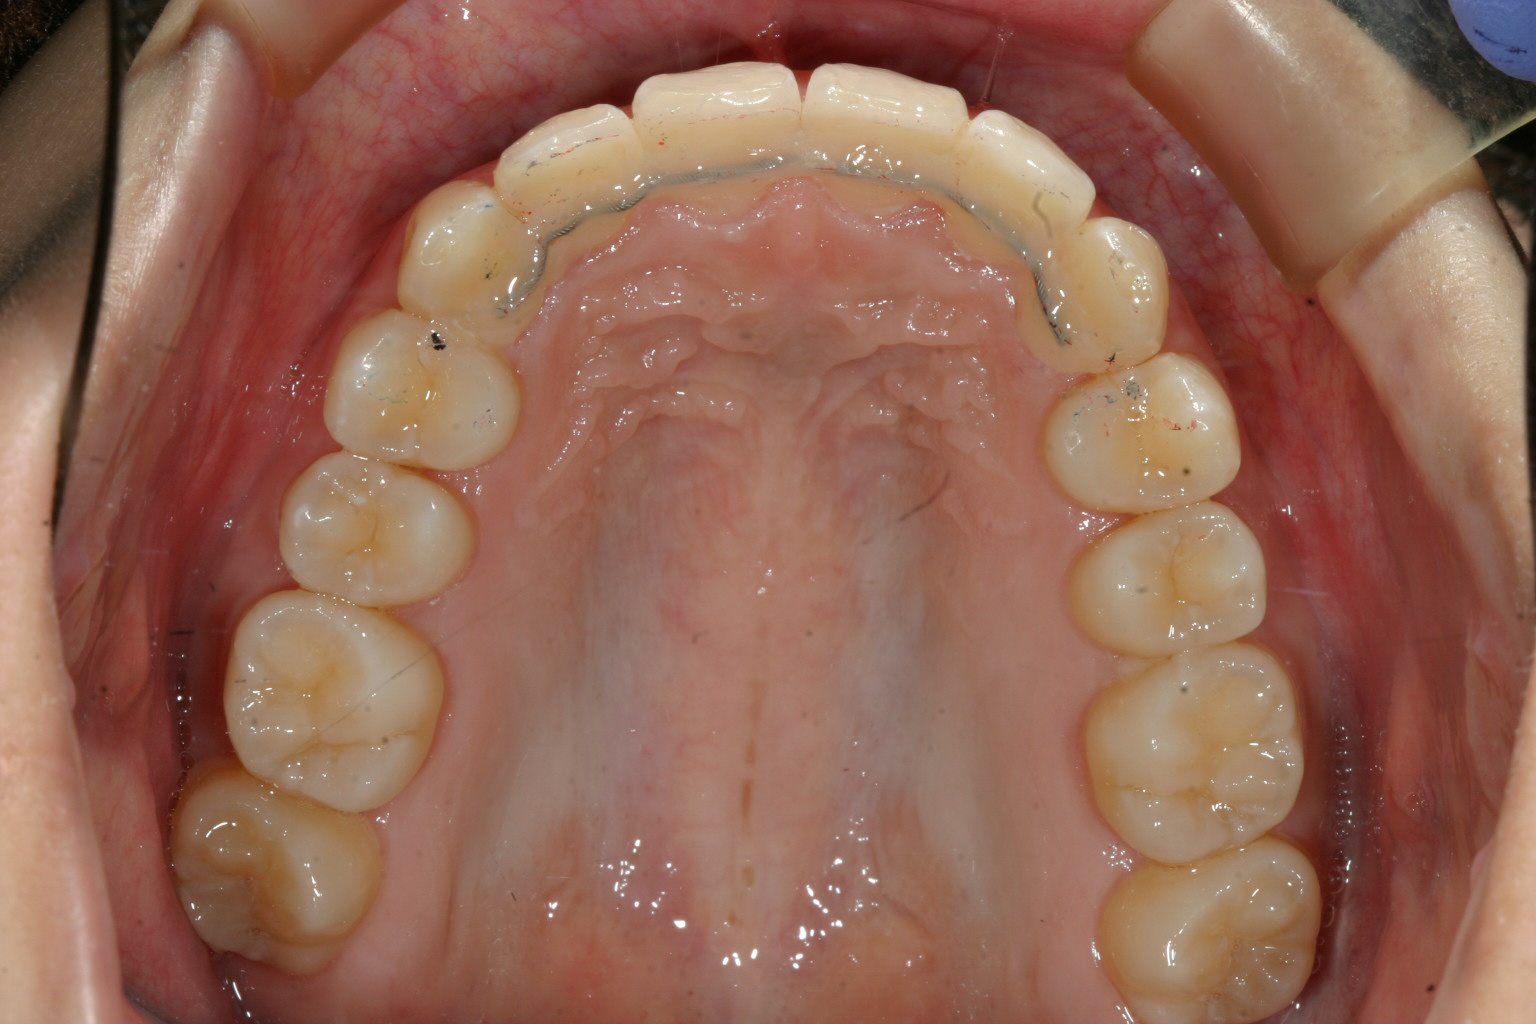

上顎きれいに並びました。 最終リテーイナーとしてワイヤーで止めています。